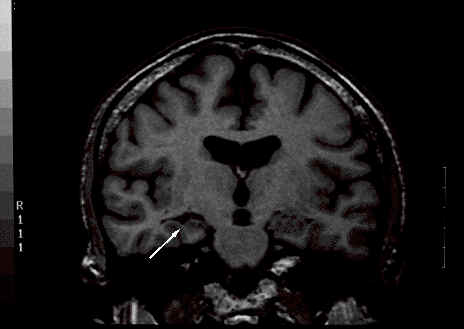

Como exemplo, vê-se abaixo uma RM de um paciente com epilepsia do lobo temporal e esclerose mesitemporal (EMT) (seta).

Fig EMT:

Os estudos inicias de RM do lobo temporal em pacientes  com   epilepsia, mostravam que as duas principais características da EMT eram atrofia unilateral das estruturas hipocampais.